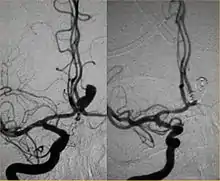

Endovascular modalities for intracranial aneurysms[2]

Between the end of the 1980s and the beginning of the '90s, INR was suddenly revolutionized after the work of two Italian physicians: Cesare Gianturco and Guido Guglielmi. The first combined a deep knowledge of diagnostic radiology with a great ability to solve technical and manual problems. He invented Gianturco's coils, which he used to make the first attempts to embolize arteries and aneurysms.[8] Gianturco also patented the first endovascular stent approved by the American FDA;[8] a device with a great legacy. In the second half of the 1980s, Sadek Hilal was the first in Columbia University to use coils to treat brain aneurysms; but this technique was inaccurate and dangerous because the coils were released with little control with great risk of occluding the vessel from which the aneurysm originated (parent vessel).[9] The coil embolization was revolutionized by the work of Guido Guglielmi in UCLA, who realized that electricity could function as a controlled release mechanism for coils; in 1991 he published two works dealing with the embolization of brain aneurysms by means of detachable platinum coils[10] (Guglielmi's coils). The treatment of aneurysms was thus made more accessible and safe.

From the early 2000s, intracranial stents were used to prevent the coils inside the aneurysmal sac from protruding into the parent artery.[11][12] Flow diversion devices were later developed, with the function of reconstructing the vessel's normal anatomy without directly closing the aneurysm neck and therefore preserving side branches and preventing ischemia.[13] The sole stenting[14] procedure involves the insertion of a stent only (without any coils) into the vessel that has an aneurysm.[15]